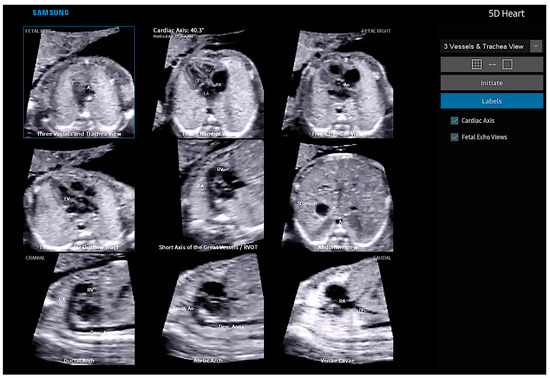

Fetal Intelligent Navigation Echocardiography (FINE), also known as “5D Heart” or “5D”, presents nine standard fetal echocardiographic views by performing cardiac volume acquisition from a 4C chamber view of the fetal heart (Figure 3) [11]. Currently, with the advent of “artificial intelligence”, the addition of this technology to 5D Heart can provide alerts for possible CHD in the images obtained via automatic reconstructions of the cardiac ultrasound views. Artificial intelligence is a promising technological innovation that can alert non-specialists to the suspicion of CHD, provide automatic measurements of image acquisition, and reduce the differences between inter-observer measurements.

Figure 3.

Fetal Intelligent Navigation Echocardiography (FINE), also known as “5D Heart”, on a normal heart. Note the automatic reconstruction of the 9 standard views of fetal echocardiography from a 4-chamber view. LV: left ventricle; LA: left atrium; RA: right atrium; RV: right ventricle; Ao: aorta; PA: pulmonary artery; SVC: superior vena cava; IVC: inferior vena cava; RVOT: right ventricle outflow tract.